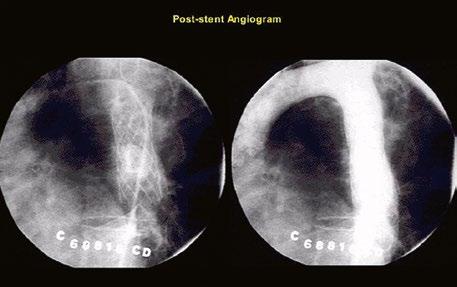

Katetrizační léčba valvární PS spočívá v balonkové valvuloplastice u dětí i u dospělých, která může být i opakovaná. Pro balonkovou valvuloplastiku nejsou vhodné dysplastické a kalcifikované chlopně ani chlopně s významnou regurgitací. Katetrizační implantace bioprotézy se v současnosti používá pro dysfunkční konduity nebo zdegenerované bioprotézy („valveinvalve“) (viz Fallotovu tetralogii, kap. 45.9.5). Supravalvární PS a periferní stenózy větví plicnice mohou být řešeny angioplastikou s případným zavedením stentu.

Supravalvární pulmonální stenóza a stenózy větví plicnice bývají součástí komplexních VSV (např. Fallotovy tetralogie) nebo syndromů (Williamsův syndrom, syndrom Noonanové, syndrom vrozené rubeoly, Alagillův syndrom aj.) (Obr. 45.39). Získané stenózy větví plicnice, ale i úplný uzávěr větve plicnice můžeme vidět po spojkových operacích podle BlalockaTaussigové (Obr. 45.40, Obr. 45.41). Pro zobrazení supravalvárních a periferních stenóz plicnice je optimální CT angiografie (Obr. 45.40, Obr. 45.41, Obr. 45.42, Obr. 45.43).